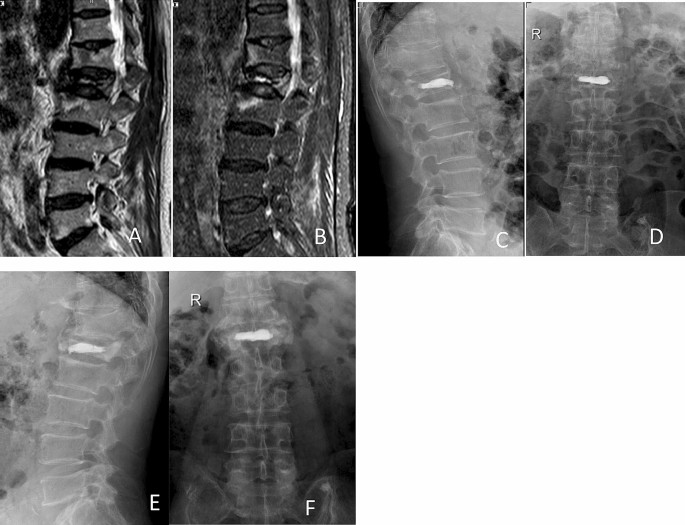

PVP: High-viscosity bone cement was adjusted to wiredrawing stage according to the instruction, and was then injected into vertebral body with special hydraulic propulsion pump (Fig. 1).

Preoperative and postoperative films of a 65-year-old woman with OVCFs of L1 vertebral body, treated with high-viscosity cement PVP. Preoperative sagittal MR image showing significant loss of the anterior vertebral body height at the L1 level (A), (B). Anterior–posterior and lateral films showing no leakage of bone cement postoperatively (C), (D) and at 1 year postoperatively (E), (F).